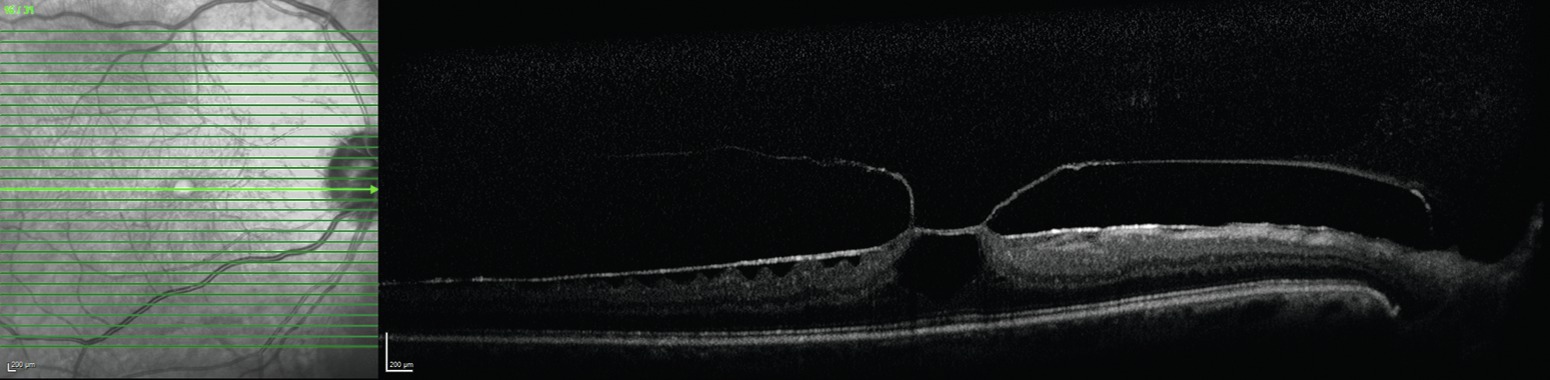

L'adhérence persistante du vitré à la rétine peut provoquer un certain nombre de situations pathologiques. La contraction du vitré ainsi que les tractions provoquées par les saccades oculaires peuvent conduire à des déchirures, en particulier au niveau du bord postérieur de la base du vitré. L'adhérence persistante au niveau de la macula peut être responsable de traction vitréomaculaire, ainsi que de la formation de trou maculaire (fig. 16-1). Les « reliquats » de la membrane hyaloïde postérieure restent souvent attachés à la membrane limitante interne après un DPV. Pour cette raison, certains experts pensent qu'un DPV présumé est souvent un « vitréoschisis » postérieur. Ces reliquats de vitré peuvent jouer un rôle dans la formation de membrane épirétinienne ou de trou maculaire. Ils peuvent également contribuer à des décollements de rétine tractionnels chez les patients atteints de myopie pathologique et à des œdèmes maculaires chez les patients diabétiques. Des adhérences persistantes du cortex vitréen postérieur peuvent être mises en évidence lors de la chirurgie par marquage par des cristaux de triamcinolone injectés dans la cavité vitréenne (fig. 16-2).

Figure 16-1

Représentation tridimensionnelle de la tomographie en cohérence optique spectral domain (SD-OCT) du syndrome de traction vitréomaculaire (TVM). Le cône de vitré est attaché et surélève la fovéa centrale.

(Remerciements au Dr Richard F. Spaide.)